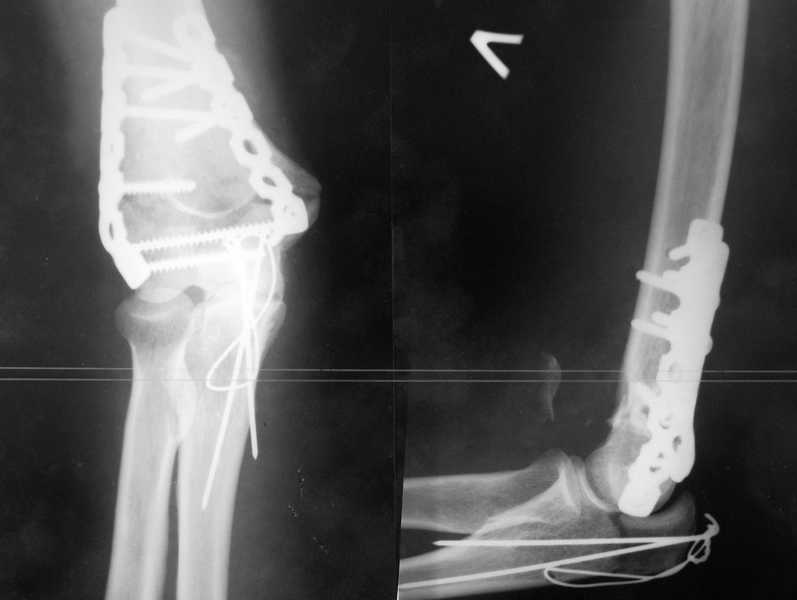

У пациентки 42 лет после операции остеосинтеза чрезмыщелкового перелома плеча, выполненной в нашей клинике 2 месяца назад, на контрольных R-граммах имеется гетеротопический оссификат по передней поверхности плеча.

Оперирована по методике АО, после операции максимально рано начала заниматся ЛФК. В настоящее время основная жалоба пациентки на ограничение сгибания в локтевом суставе. Клинически объем движений: сгибание 90 градусов, разгибание 170 градусов, ротационные движения в полном объеме. Привожу снимки сразу после операции и через 2 месяца. (На рентгенограммах после операции в мягких тканях по передней поверхности плеча имеется небольшой костный фрагмент, но его ширина во фронтальной плоскости не более 1 мм., обнаружен был по снимкам после операции. Интраоперационно основные крупные фрагменты отрепонировались хорошо, объем движений был сгибание до 75 градусов, разгибание 175 град.) Пациентка неудовлетворена объемом сгибания, хотя была предупреждена о высокой вероятности ограничения движений. Профилактика гетеротопической оссификации (прием индометацина) не проводилась, т.к. имелась язвенная болезнь, да и эффект от его приема считаю сомнительным.